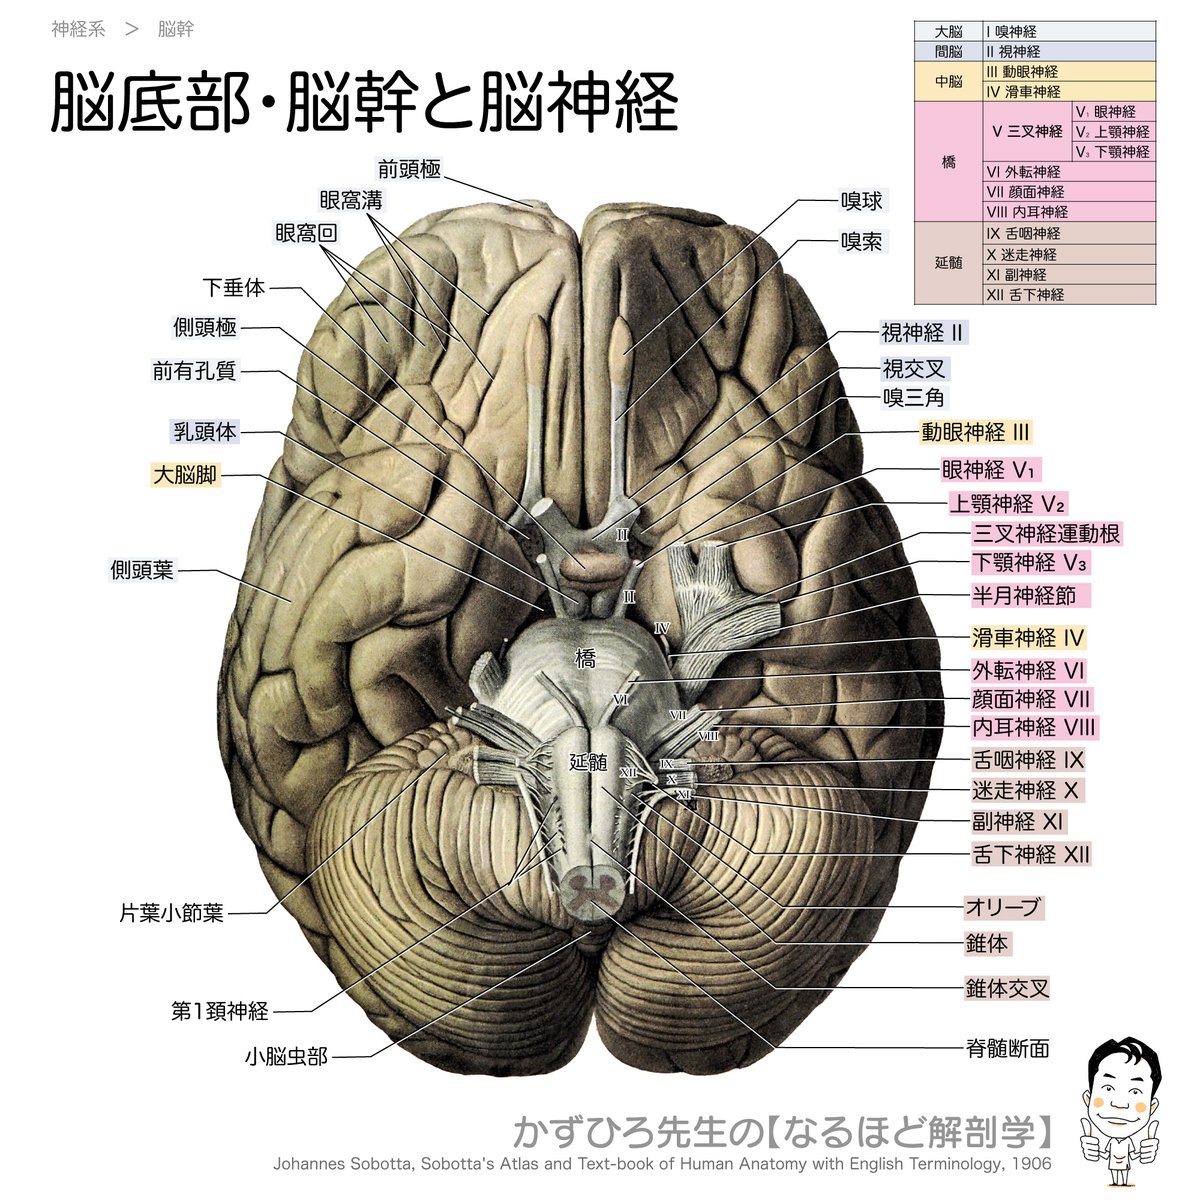

脳神経画像解剖ナビゲーション: 正常・変異・異常との比較で読影。脳の機能解剖とリハビリテーション | 金子 唯史 |本 | 通販 | Amazon。脳神経画像解剖ナビゲーション: 正常・変異・異常との比較で読影。金芽ロウカット玄米 2kg x4袋 東洋ライス。「脳神経画像解剖ナビゲーション = NAVIGATION OF IMAGING ANATOMY:CENTRAL NERVOUS SYSTEM : 正常・変異・異常との比較で読影に役立つ!」岡本 浩一郎 / 岡本 浩一郎定価: ¥ 9400#岡本浩一郎 #岡本_浩一郎 #岡本浩一郎 #岡本_浩一郎 #本 #自然/医療・薬学・健康○ 裁断について業者による裁断後の商品です。脳神経画像解剖ナビゲーション 正常・変異・異常との比較で読影。裁断済みのため、商品の状態は\"全体的に悪い\"にしています。ケーススタディで学ぶ 脳動脈瘤クリッピングの5ステップ - 株式。裁断について御理解のある方のみでお願い致します。メジカルビュー社|脳神経外科|エッセンシャル頭蓋底外科[Web。○ その他状態についてマーカーや書き込みはなしですが、素人検品である旨をご承知おき下さい。脳卒中後の病的な痛みに関連する大脳皮質の縮小信号を検出。スキャナ読み込みの段階でページの入れ替わりが稀にありますが、抜けはございません。01 脳のvascular territoryと脳葉の画像解剖 | 画像診断情報。ご確認ください。リハに活かす!機能解剖から学ぶ脳画像の読み方〜症状・経過。○ その他注意点返品・交換は承っておりません。NEXT FIELD 5:異分野間の連携が革命を起こす〜Mayaを操る脳神経。ご了承ください。Untitled Page。素人管理であることをご理解の上、ご購入ください。脳手術 AIシミュレーター『Hana』 – ポケクエ。他の商品と同時購入でしたら割引いたします。産科と婦人科増刊号 ホルモン療法 裁断すみ。その他なにかご要望ありましたら、気軽にコメントください。世界の見方の転換1、2、3。